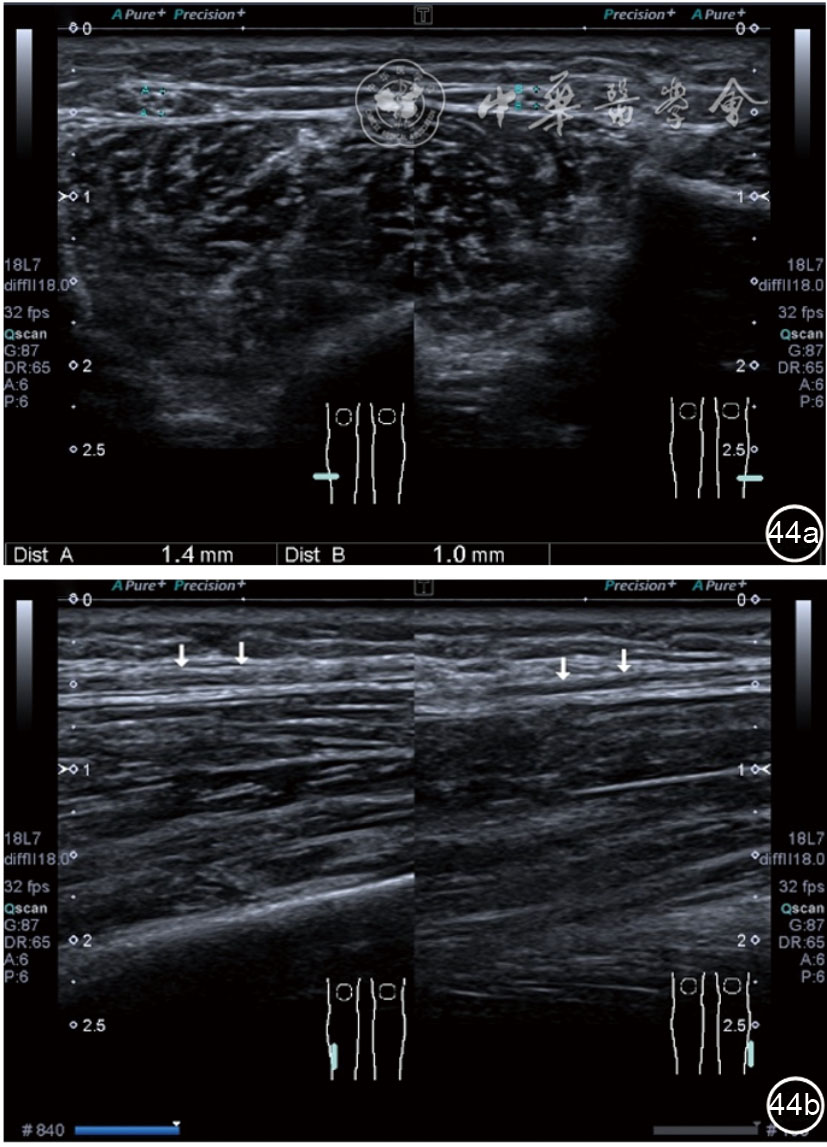

患者采取侧卧位,患肢在上,屈膝20°。应用10~18 MHz高频线阵探头,扫查深度1~3 mm。长轴和短轴结合双侧对比扫查。超声影像学所见:短轴可见卡压腓总神经近端增粗,面积增大;长轴可见腓总神经卡压处变细,其近侧肿胀、回声减低,而在卡压远侧则表现正常(图35);一些受压严重者可以出现神经周围积液,卡压神经部位的筋膜增厚(图36);受压神经内血流增加对临床诊断意义更大(图37);探头在病变神经处加压常可引起神经刺激症状。腓总神经支配的肌肉有失神经支配改变,表现为肌肉回声增高和肌肉萎缩(图38)。

图38 肌肉回声增强和肌肉萎缩超声图像